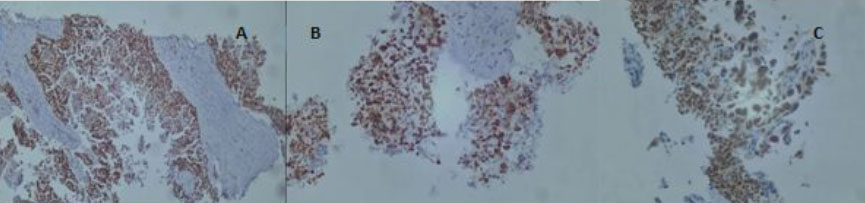

The immunohistochemical study showed tumor cells positive for WT1, P53, and PAX 8 and negative for GATA3, TTF1 (Figure 3).

Figure 2: The immunohistochemical study showed tumor cells positive for WT1, P53, and PAX 8 and negative for GATA3, TTF1.

Figure 3: Histological section (magnification × 100): tumor cells are pleomorphic with large hyperchromatic nuclei and a high nucleocytoplasmic ratio.